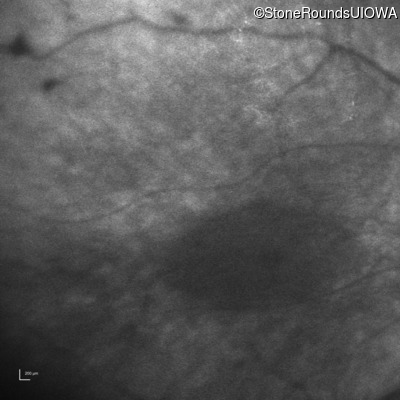

Infrared Fundus Photograph - Right - Light Perception

Exemplar

Infrared Fundus Photograph - Left - Light Perception